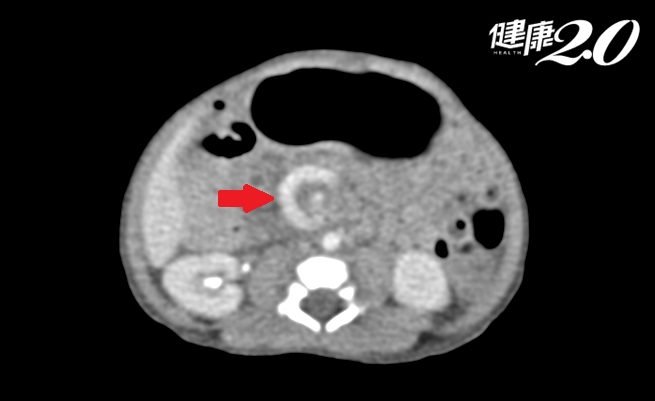

▲寶寶腸子從根部扭轉,血管呈迴旋狀。

造成中腸扭轉的原因,大多是因為病人有先天性腸子旋轉不良,造成十二指腸腸系膜根部及升結腸處被腹膜沾黏包覆,使腸子從根部扭轉,導致十二指腸阻塞及小腸缺血壞死。急性中腸扭轉多發生在新生兒時期,最典型的症狀是出生後能正常喝奶排便,但3~5天後突然發生大量膽汁性嘔吐。